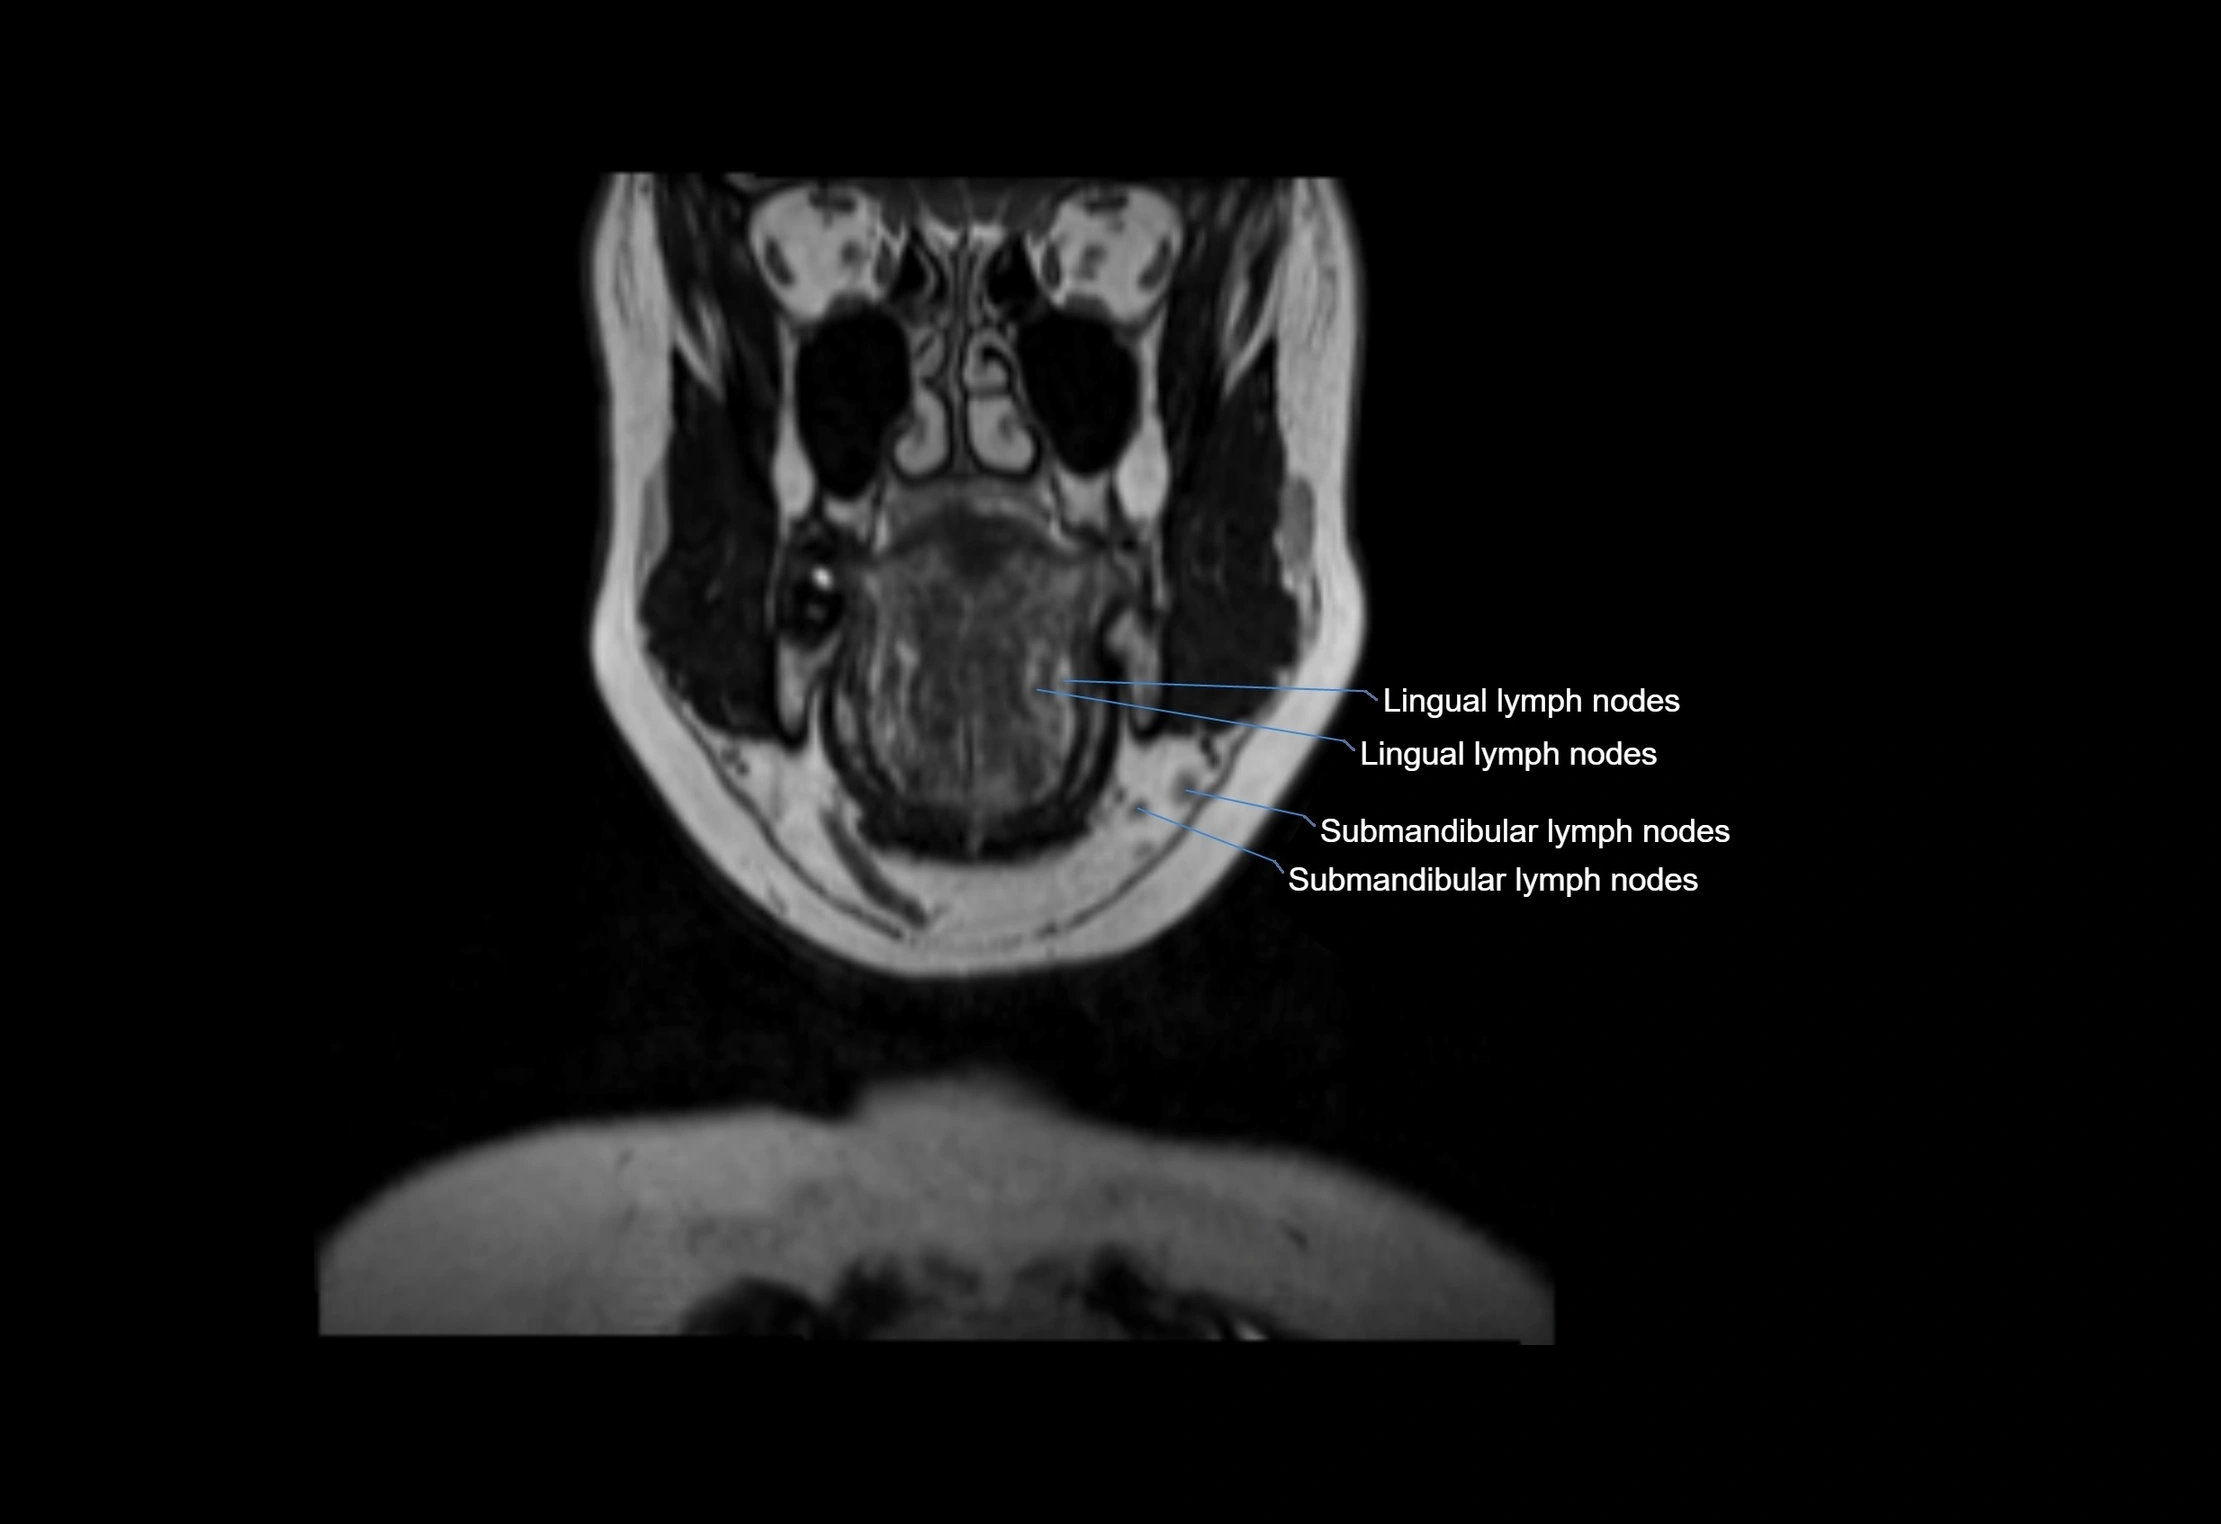

Accessory lymph nodes are small, secondary lymph nodes located along the main facial and cervical lymphatic chains, often adjacent to primary lymph nodes, such as preauricular, submandibular, or occipital nodes. They are typically less than 5 mm in diameter, embedded within subcutaneous fat or connective tissue, and may be variable in number and location. These nodes provide additional filtration and immune surveillance for lymph collected from the face, scalp, and neck regions. Accessory lymph nodes are usually non-palpable in healthy individuals but may enlarge in response to infection, inflammation, or metastasis, making them clinically significant.

Location

• Found along primary lymph node chains, including preauricular, submandibular, parotid, and occipital regions

• Embedded in subcutaneous fat or superficial fascia, often lateral or posterior to primary nodes

MRI Appearance

T1-weighted images:

• Normal accessory nodes appear as small, oval hypointense to intermediate signal structures within subcutaneous fat

• Surrounded by hyperintense fat, enhancing contrast for visualization

T2-weighted images:

• Nodes show intermediate signal, with surrounding fat bright

• Useful for detecting edema, inflammation, or infiltration

• Fatty hilum may appear slightly hyperintense relative to cortex

MRI images